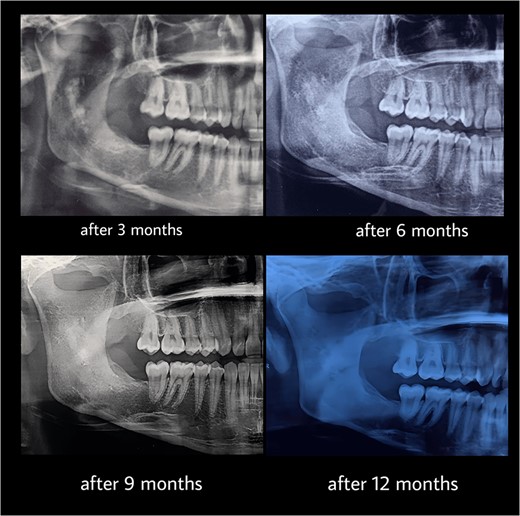

Under general anesthesia, an incision was made around the fistula to remove the overlying mucosa and expose the lesion. A 1 cm size window was made into the cyst cavity (Fig. 3). The cyst lining was sutured to surrounding mucosa. The cavity was kept open using a povidone iodine-saturated gauze, and it was replaced every 2 weeks. Follow-up radiograph (OPG) was recommended after 3, 6, 9 and 12 months (Figs 4 and 5).

Computed tomography after 12 months showed a bone regeneration in the lesion’s area and the cystic lesion has become completely surrounded by thick bony plates.

After 12 months, the second stage was performed to remove the lesion (Fig. 6). Under general anesthesia, enucleation with peripheral ostectomy was performed. A flap was developed to expose the anterior border and most of the lateral surface of ramus. The lining of the lesion was detached from the bony walls. A surgical bur was used to remove bone adjacent to the cystic lining. After enucleation, the cavity was filled with gelfoam and the incisions were closed with 4–0 Prolene suture. The patient returned regularly for follow-up after every 3 months (Fig. 7). The total follow-up period so far was 36 months. Cone beam computed tomography (CBCT) scan after 24 and 36 months showed no evidence of lesion recurrence and great bone formation (Fig. 8).